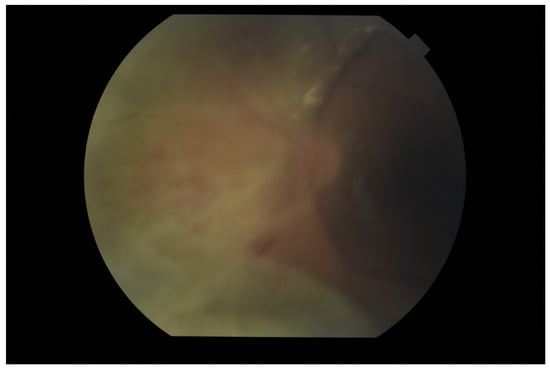

The tendency to abscess formation in the course of Klebsiella infection is also reflected in eye. One of the rare but characteristic feature of EE in the course of Klebsiella infection is the formation of subretinal abscesses [26]. They take the form of retinal elevation and paleness (Figure 1 and Figure 2). With properly selected antibiotic therapy, even large abscesses may be absorbed. If the patient is undergoing vitrectomy, intraoperative drainage may be considered [27].

Fundus pictures of subretinal abscess, taken on the second day after vitrectomy. Partially drained abscess is visible, located nasally from the optic disc. Poor image quality is caused by the presence of inflammatory cells in the anterior chamber.